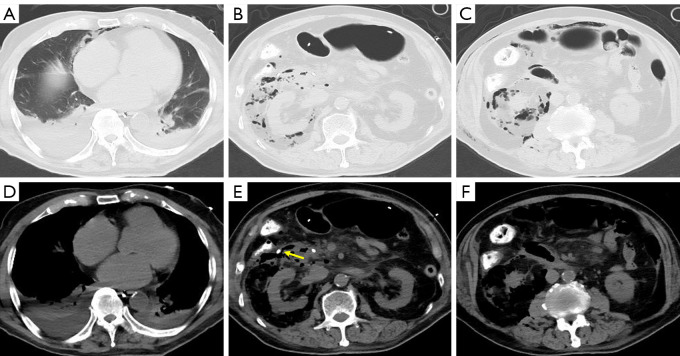

Case description: This retrospective study reviewed seven cases showing duodenal perforation after ERCP for choledocholithiasis between 2019 and 2024. The patients showed clinical symptoms such as fever, abdominal pain, and abdominal distension within 1-3 days after ERCP, and were managed with the interventional three-tube method (insertion of a nasointestinal feeding tube for enteral nutrition, a gastrointestinal decompression tube, and a percutaneous drainage tube for drainage of pus and air). After 5-7 days of hospitalization, the patients were discharged upon stabilization. All patients showed successful healing of duodenal perforation during follow-up.